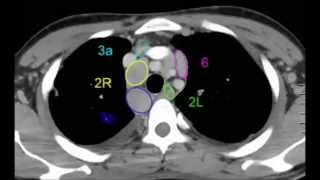

La pathologie tumorale médiastinale : Démarche Diagnostic et thérapeutique (partie 2)

La pathologie tumorale médiastinale (partie 2): Principales Etiologies et Moyens Thérapeutiques- Pr.Marouf Rachid - Chirurgie Thoracique -CHU Mohamed ...

La pathologie tumorale médiastinale : Démarche Diagnostic et thérapeutique (partie 1)

La pathologie tumorale médiastinale (partie 1) - Pr.Marouf Rachid - Chirurgie Thoracique -CHU Mohamed VI-Oujda Ce cours est destiné aux étudiants de 2éme ...

ECNi.fr Maitriser l'interprétation des clichés /Cancer Bronchiqe + adénopathie

Le cancer primitif des bronches est une tumeur maligne prenant son origine dans la muqueuse des bronches. C'est l'un des cancers les plus fréquents chez ...